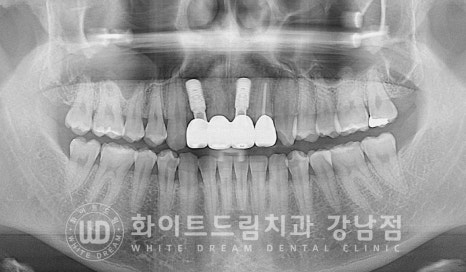

▲ 앞니 3개가 사고로 탈구된 상태 / 앞니 빠짐 임플란트

환자분의 초진 x-ray 사진입니다.

상악 앞니 3개(22, 21, 11번 치아)가 빠져있고

그 옆 22번 치아는 치아머리 반이 부러진 상태입니다.